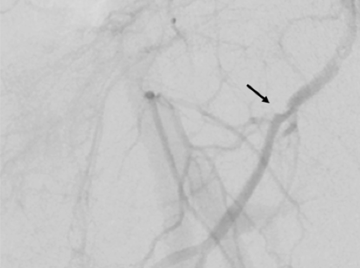

01. Zwischen den beiden Pfeilen ist eine starke Verengung (Stenose) der linken Penisarterie (Arteria pudenda interna) zu erkennen. Sie ist die Ursache dafür, dass der Penis nicht ausreichend mit Blut versorgt wird.

02. Dieses Bild zeigt die gleiche Arterie, während sie mit einem Ballon geweitet wird. Mediziner bezeichnen diese Methode als Ballondilatation oder Ballonangioplastie.